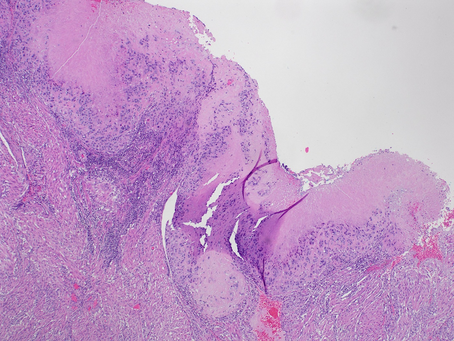

GYN Case 2. Hysterectomy from a young patient in 20s

•Diagnosis: epithelioid trophoblastic tumor